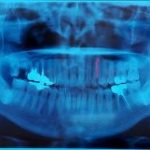

そのほかに、排出管(唾液が出る管)の周囲の炎症や発赤、また排出管の出口からの排膿(膿が出る)がみられることもあります。ただし唾石症では症状がまったくでないケースも多く、別の病気で撮影したレントゲンやCT検査などで偶然見つかることも少なくありません。

唾石症が疑われるケースでは、まず医師または歯科医師が患部を直接指で触って唾石の存在を確認します。その後、レントゲンやCT検査で唾石の詳しい位置や大きさ、個数などを確認していきます。検査にかかる時間は15〜20分程度です。